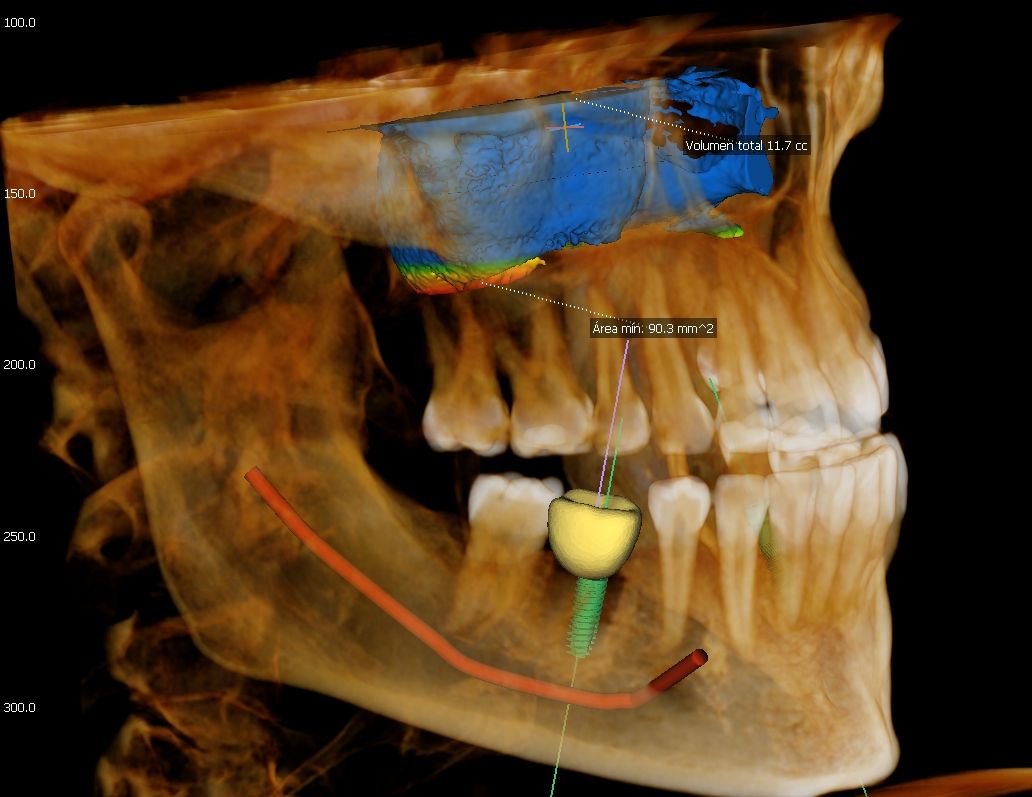

Green 16/18 ofrece una gama de campos de visión seleccionables. Multi FOV permite al usuario seleccionar el modo FOV óptimo y minimizar la exposición a áreas que no son la región de interés. Seleccione el tamaño adecuado de FOV entre 16×9/18×10, 12×9/13×10, 8×9 y 5×5 basado en una particular necesidad de diagnóstico.

Cubre la región del arco completo, seno y la ATM izquierda / derecha y es adecuado para la mayoría de los casos de cirugía oral así como la cirugía de implantes múltiples. También puede medir el volumen de la vía aérea.